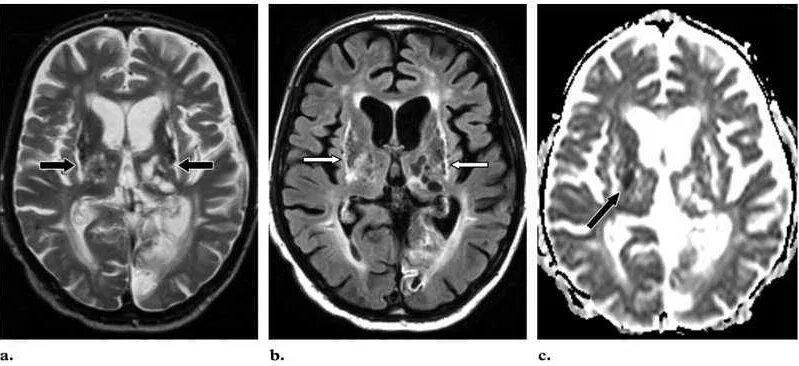

Что значит пространства вирхова робина